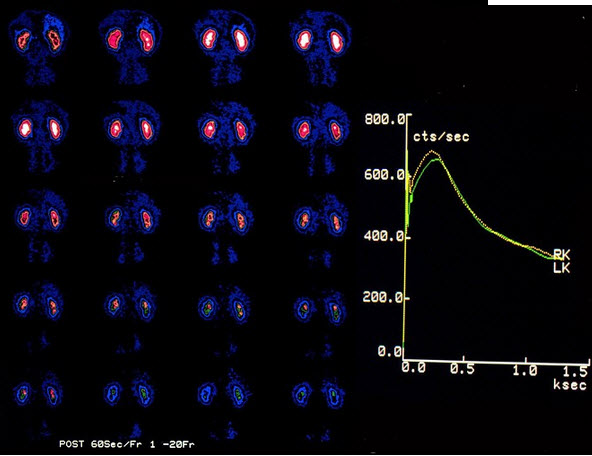

一男性,45岁,体检行(99)Tc(m)-DTPA肾动态显像如图,正确的诊断是()A: 双肾动脉血流灌注正常B: 左侧肾动脉狭窄C: 右侧肾动脉狭窄D: 双肾实质功能正常E: 右侧尿路梗阻

一男性,45岁,体检行(99)Tc(m)-DTPA肾动态显像如图,正确的诊断是()

- A: 双肾动脉血流灌注正常

- B: 左侧肾动脉狭窄

- C: 右侧肾动脉狭窄

- D: 双肾实质功能正常

- E: 右侧尿路梗阻